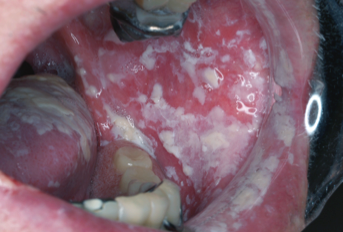

カンジダ口内炎

出典

img

1: 著者提供